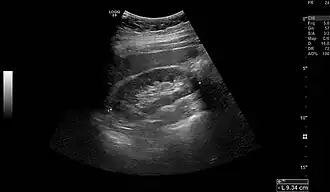

Normal adult right kidney as seen on abdominal ultrasound with a pole to pole measurement of 9.34 cm -

A Danish study measured the median renal length to be 11.2 cm (4+7⁄16 in) on the left side and 10.9 cm (4+5⁄16 in) on the right side in adults. Median renal volumes were 146 cm3 (8+15⁄16 cu in) on the left and 134 cm3 (8+3⁄16 cu in) on the right.[17]